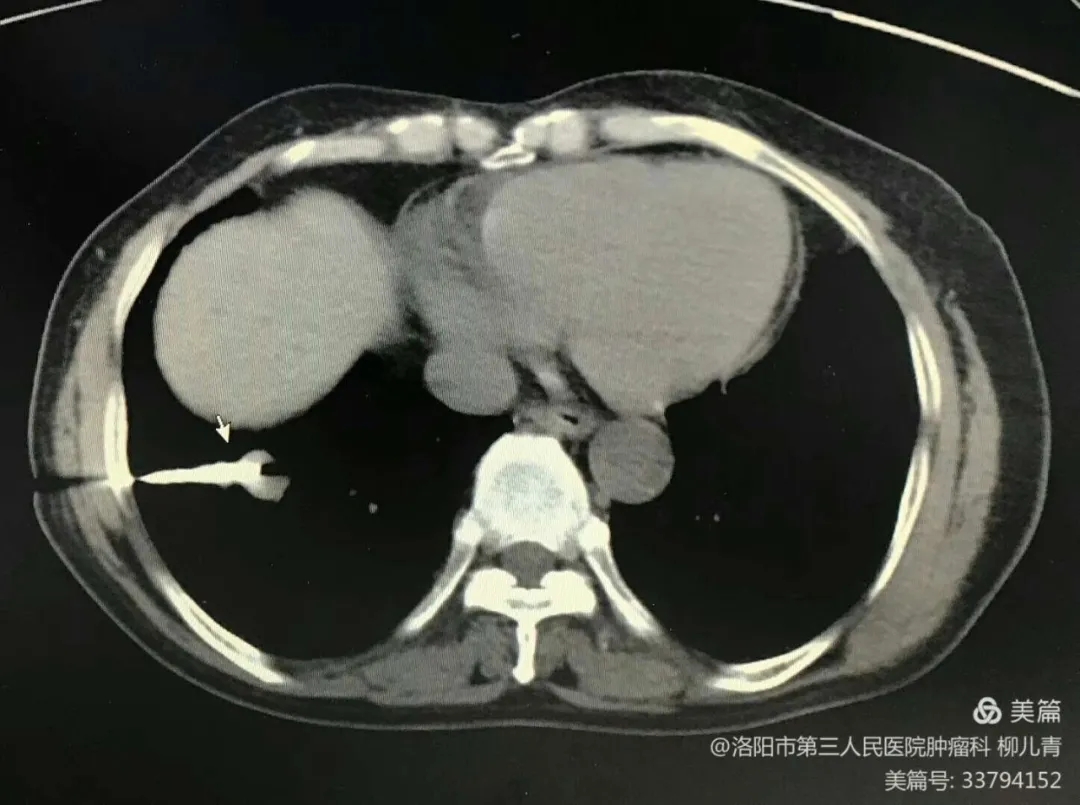

随着影像学诊断设备的不断发展,对肺部疾病尤其是肺癌的诊断有了很大进展,经皮肺穿刺活检术对人体创伤性小,可反复操作;可以清楚显示肺内病变的大小、外形、位置;准确显示病变与周围组织的空间关系,准确定位,随时监测穿刺针的具体位置和进针方向,成功率高,较为安全。